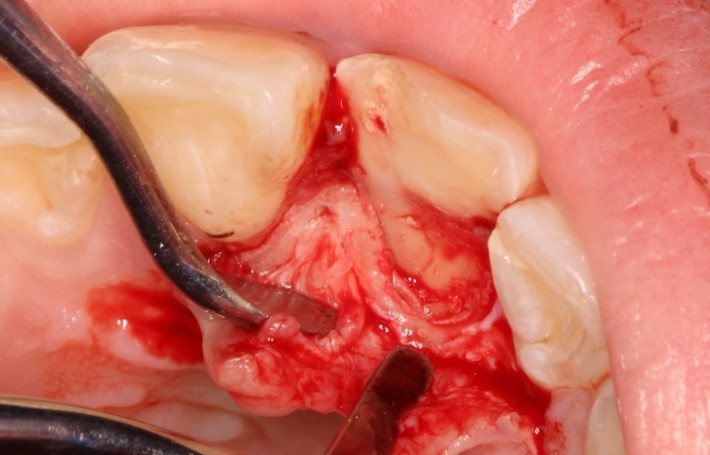

Лечение: Под местной анестезией убрали часть сколотого зуба

Отслоили мягкие ткани (а)

Редуцировали часть костной пластинки (б)